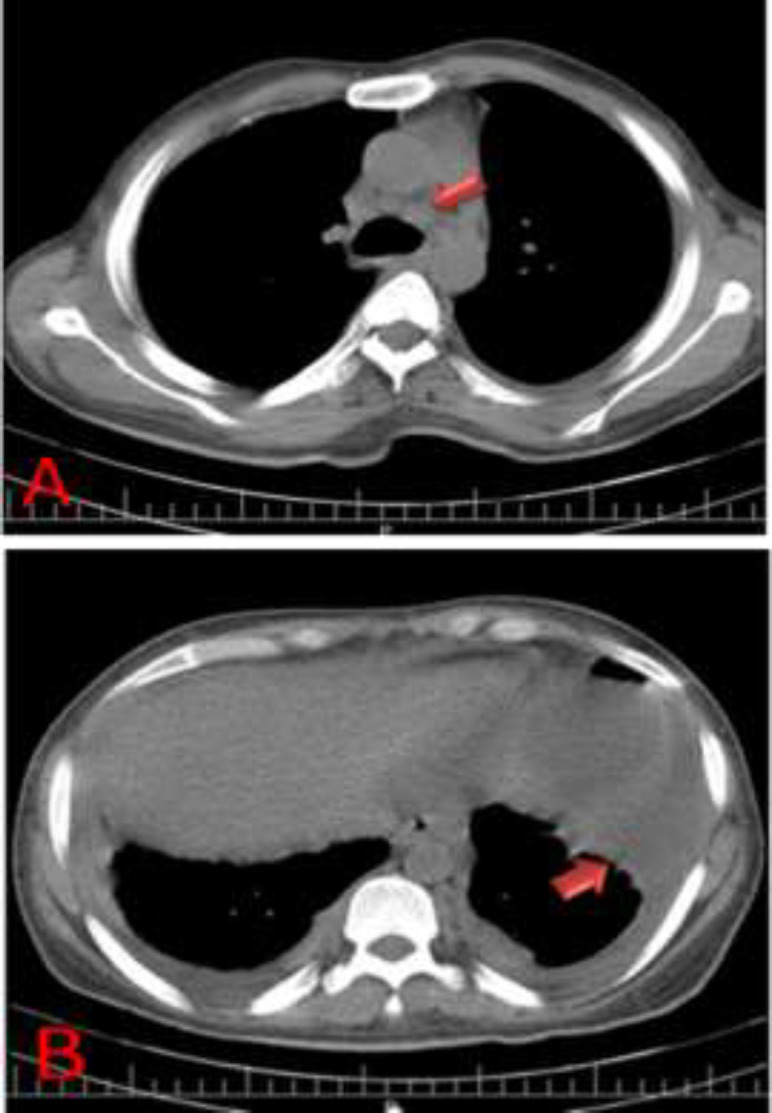

Case presentation: Herein, we present a Persian male adult who manifested with epigastric pain, weakness, and a history of pleuritic chest pain two months prior to admission. The findings of the physical examination included vital signs within the normal range, unilateral fine crackle in the lung, abdominal distension with positive shifting dullness, and fluid wave test. Analysis of the ascitic fluid revealed a Serum-ascites albumin gradient (SAAG) of less than 1.1g/dl, indicating a non-portal condition. The results of the acid-fast bacilli (AFB) staining as well as the TB polymerase chain reaction (PCR) test were negative. However, the adenosine deaminase (ADA) level was 44 IU/L. A chest CT scan revealed mediastinal lymph node enlargement and pleural thickening with loculated pleural effusion. Three acid-fast bacilli smear of morning sputum were sent, and all three were negative. An abdominopelvic CT scan showed multiple periaortic and mesenteric lymph nodes of varying sizes with mesenteric haziness and accumulation of effusion in the peritoneal cavity. Eventually, peritoneal biopsy, the gold standard, was performed, which revealed multiple granulomatous lesions and areas of caseous necrosis surrounded by Langerhans giant cells and epithelioid cells.